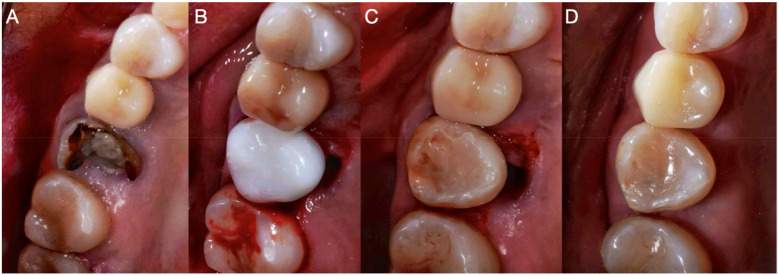

本病例报告介绍了牙齿自体移植的使用,这是一种将供体牙齿转移到同一患者的受体部位的手术,改善了功能和美学特征。与传统的修复和外科治疗(如牙种植)相比,该技术的优点被讨论。患者27岁,无相关病史,因牙髓治疗和牙源性鼻窦炎导致的骨折牙疼痛和不适进行评估。诊断出不可修复的上颌第一磨牙并拔出并替换为先前经根管治疗的上颌第三磨牙,使用3d打印复制品重塑牙槽部位。干预是成功的,之后进行了充分的临床和影像学随访3年,显示良好的骨形成和牙周韧带的连续性,没有病理性吸收的迹象。这个案例表明,如果计划和执行得当,牙齿自体移植可以成为一种有效的、生物的牙齿康复替代方法,特别是使用先进的技术,如锥体束计算机断层扫描和3d打印供牙复制品。

This case report presents the use of dental autotransplantation, a procedure in which a donor tooth is transferred to a recipient site in the same patient, improving functional and esthetic characteristics. The advantages of this technique compared to conventional prostheses and surgical treatments, such as dental implants, are discussed. A 27-year-old patient with no relevant medical history was evaluated for pain and discomfort in fractured teeth with previous endodontic treatments and odontogenic sinusitis. A non-restorable maxillary first molar was diagnosed and extracted and replaced with a previously endodontically treated maxillary third molar, for which a 3D-printed replica was used to reshape the alveolar site. The intervention was successful, after which an adequate clinical and radiographic follow-up was carried out for 3 years, showing good bone formation and continuity of the periodontal ligament, with no signs of pathological resorption. This case demonstrates that, when properly planned and executed, dental autotransplantation can be an effective and biological alternative for dental rehabilitation, especially with the use of advanced technologies, such as cone beam computed tomography and 3D-printed replicas of donor teeth.